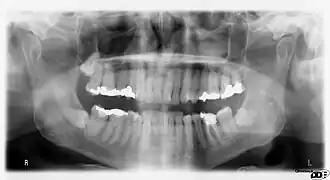

![]() (Ortopantomografía) Radiografía de la boca de un hombre. | ||

La dentición permanente inicia su erupción desde los seis años de edad aproximadamente, e irá reemplazando a los dientes de la primera dentición hasta llegar a la edad adolescente. La dentición permanente consta de 32 dientes. En la edad de 16 a 25 años pueden llegar a erupcionar los terceros molares, también llamados "muelas del juicio o cordales", cuya retención dentro de los maxilares es muy frecuente.